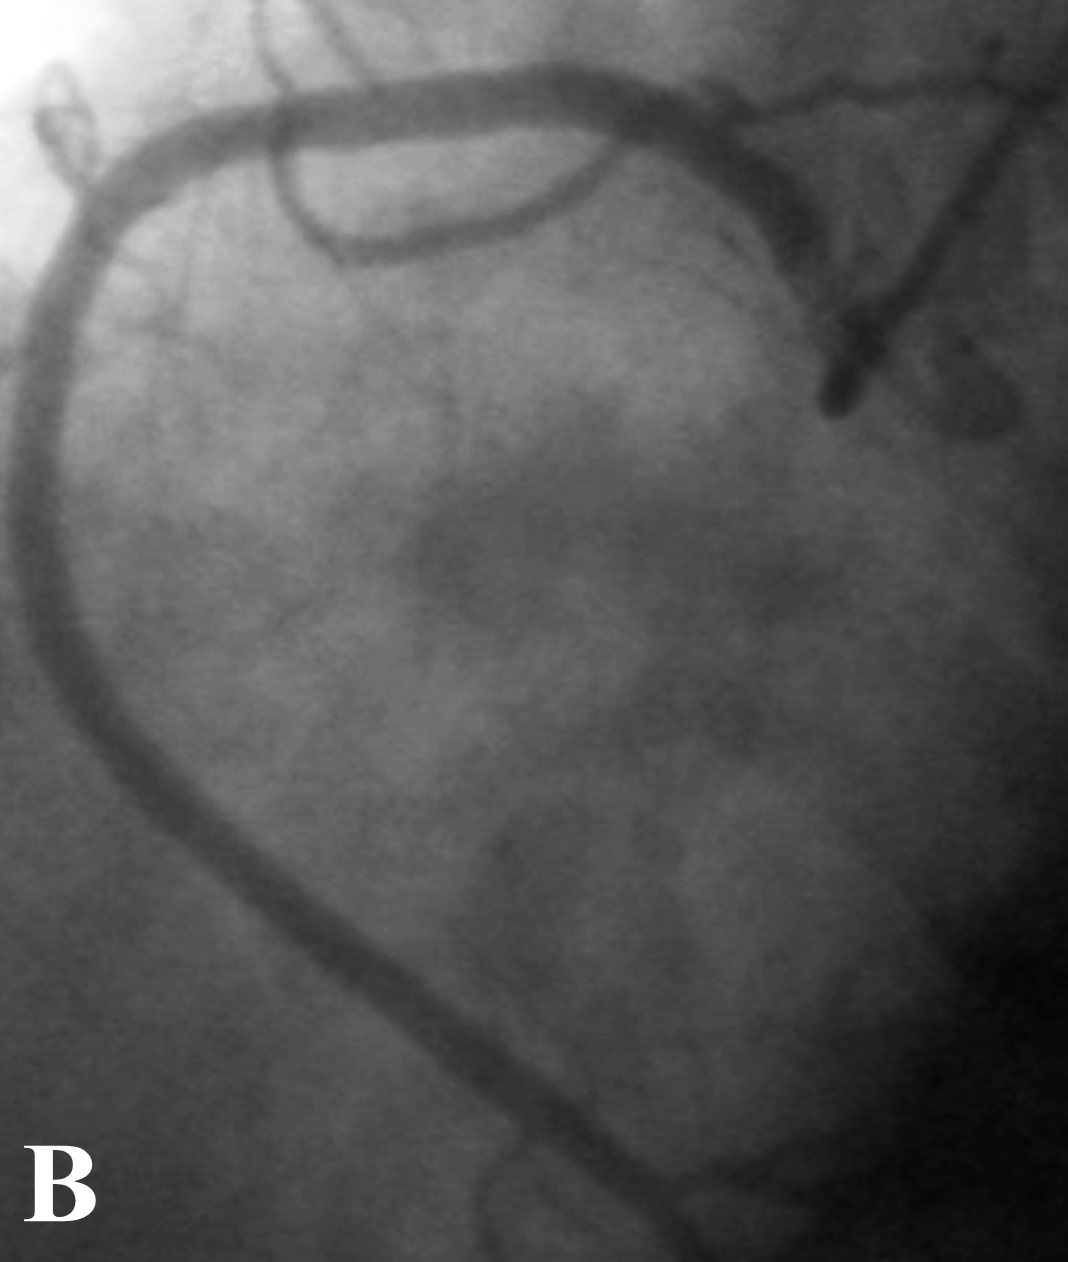

Figure 1: A. Angiographic view of Left Coronary Artery in RAO. LMCA: Left main coronary artery. LAD: Left anterior descending artery. LCx: Left circumflex artery. B. Right coronary artery in LCO. C. Angiographic view in LCO of Left coronary artery. LMCA: Left main coronary artery, LAD 1: Short Left descending artery, LCx: Left coronary artery. D. LAD 2: Long Left anterior descending artery, RCA: Right coronary artery.

Selective right coronary angiography revealed a dominant right coronary artery (RCA), without lesions (Figure 1B), during the injection, contrast media dyes unselectively an artery that comes very close to the origin of the RCA. Selective angiography of this vessel reveals that it is the middle - distal segment of the LAD which is directed right to left and return to its position on the AIVS giving a septal branch near its origin and a second diagonal branch (Figure 1D) establishing the diagnosis of a dual LAD system (Figure 1C), the proximal segment of the long LAD was narrower than the middle segment without an arteriosclerotic lesion and no compression was observed during systole. CT angiography identified the anomalous origin of long LAD from the Right Valsalva Sinus (RVS) near the origin of the RCA, and passing between the aortic root and RVOT providing a second diagonal branch without atherosclerotic lesions (Figure 2A&2B), and ending in the distal AIVS. The lesion in the posterolateral branch was successfully treated with the implant of 3.0 x 28 mm everolimus eluting stent.